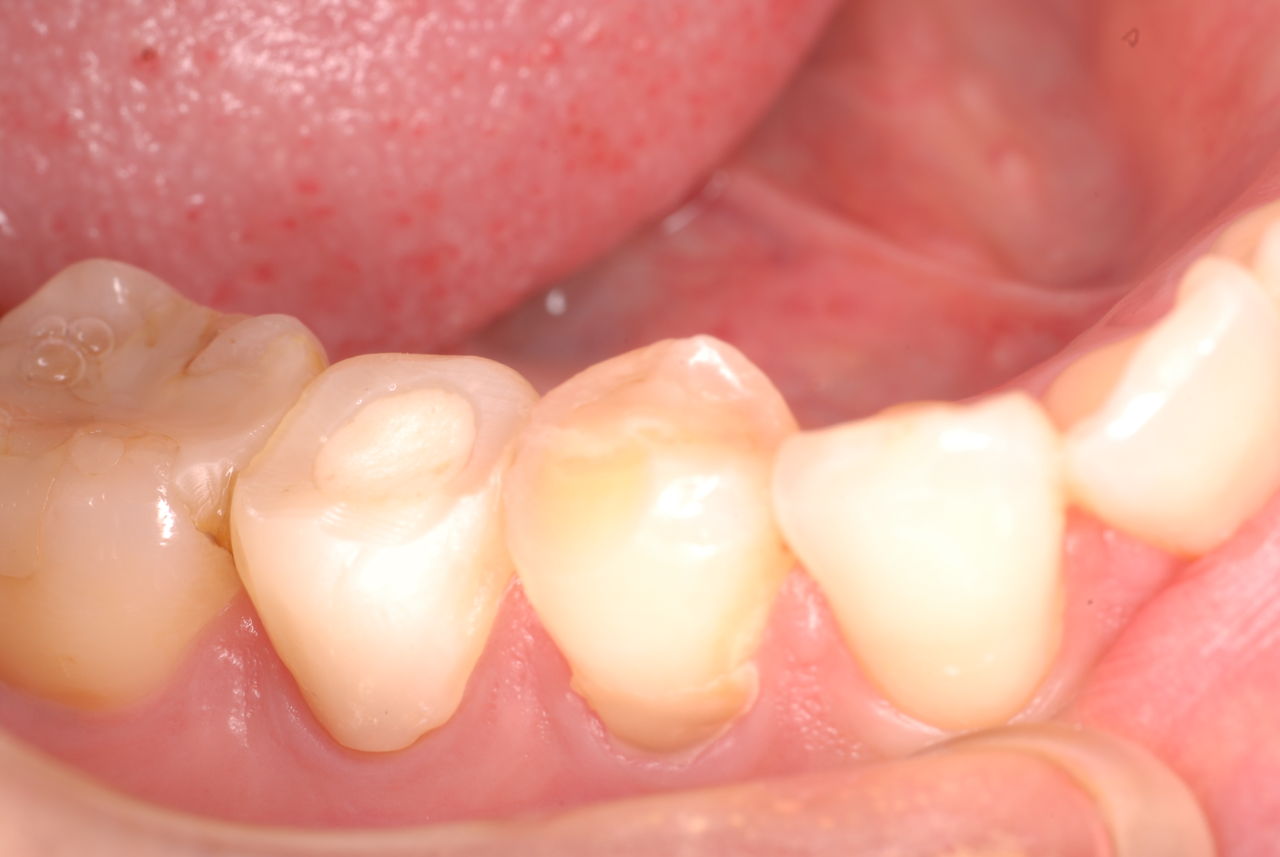

歯周病になっていましたが、少し色が黄色くなっているだけで比較的綺麗な歯の状態です。

平成9年来院神経を取り、同時に歯周病の話をしてそのまま来なくなっていたかたですが、たまたま一部欠けてきました。それで来院。